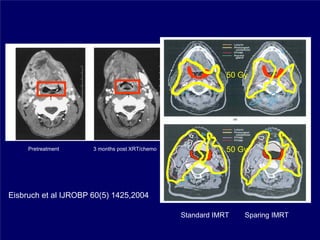

50 Gy

Pretreatment     3 months post XRT/chemo               50 Gy

Eisbruch et al IJROBP 60(5) 1425,2004

Standard IMRT   Sparing IMRT